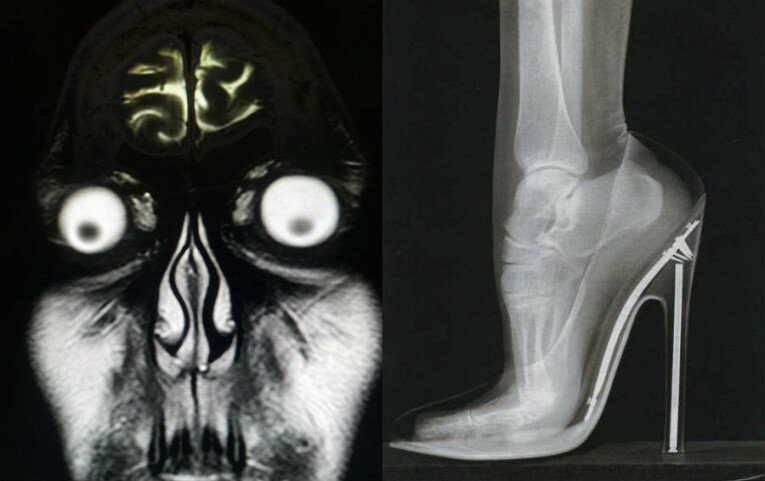

Кому-то действительно хотелось увидеть снимок головы . Наверное, всё же не стоило.

Выброшу, пожалуй, все свои туфли на каблуке.